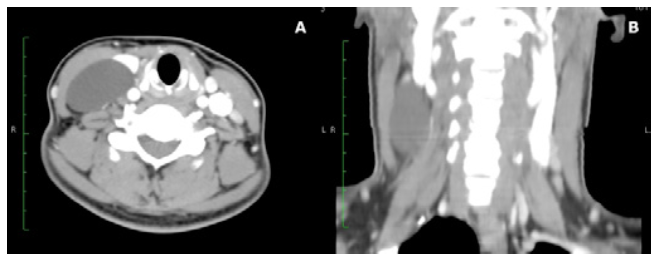

A contrast study of the neck using computed tomography (CT) showed a cystic lesion with thin walls of 55x21x43mm, which compressed the internal jugular vein, occupied the right III and IV levels and was clearly delimited by vascular and muscular structures (Figure 2).

Contrast computed tomography of the neck. A) Thin-walled cyst medial to the sternocleidomastoid muscle; B) Cystic lesion occupying the right III and IV levels.

Figure 2: Contrast computed tomography of the neck. A) Thin-walled cyst medial to the sternocleidomastoid muscle; B) Cystic lesion occupying the right III and IV levels.

Unilateral lesions composed of microcysts, delimited and extended to one or two compartments of the neck, are candidates for surgical resection, as they may be completely resected. However, the lesions located near the floor of the mouth or the parapharyngeal space are more likely to be partially resected. 6 In this patient, with no family history or genetic alterations, the lymphangioma was secondary to interruption of lymphatic drainage, probably due to previous neck trauma that went unnoticed. Similar to Gow et al.6, for this case, surgical resection of the mass was decided because the CT showed a single cyst circumscribed to the III and IV right levels of the neck (Figure 2).